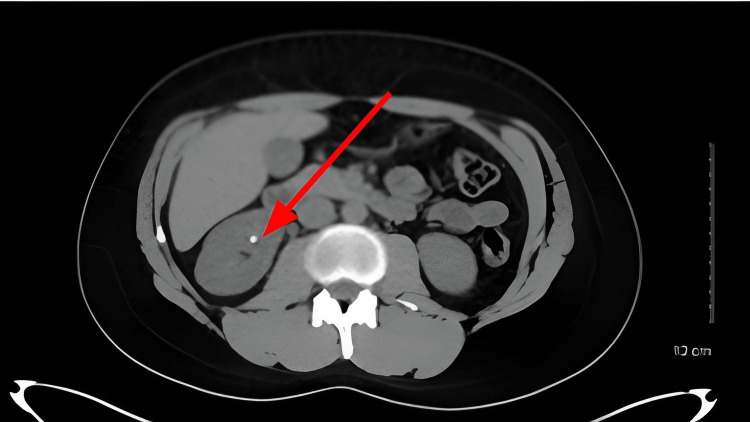

The CT scan findings are shown in Figure 1.